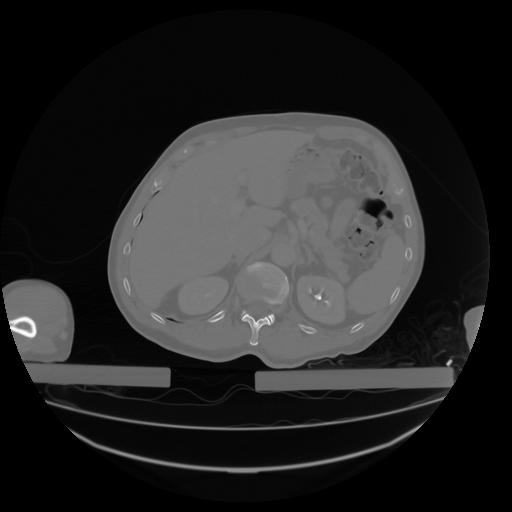

27 CUERPO,CE,Axial,3.0,CUERPO,,